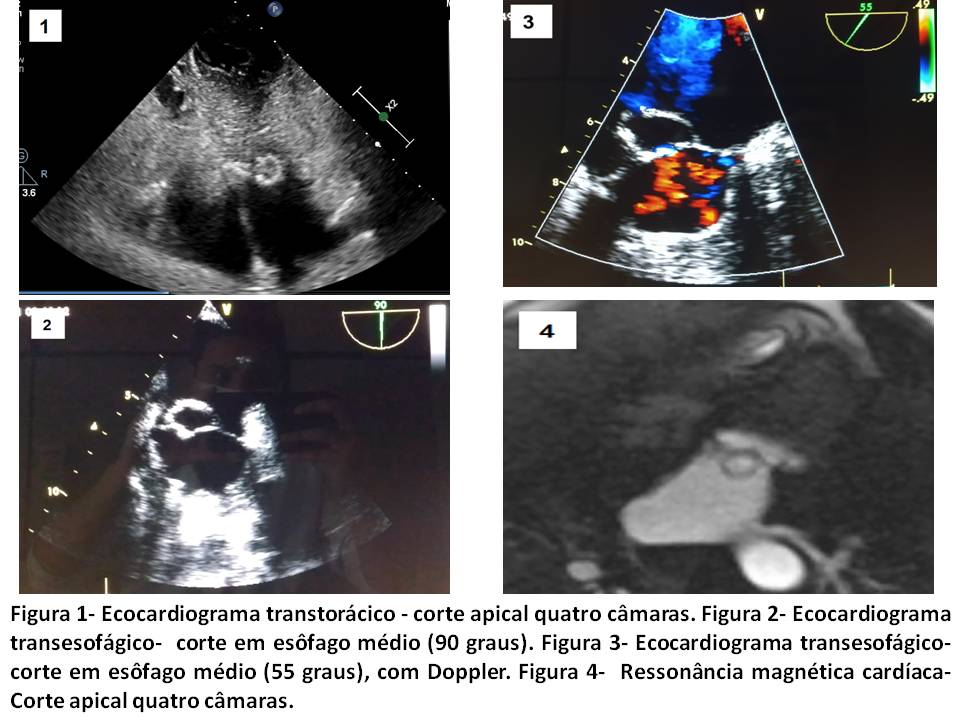

Caso: Paciente do sexo feminino, 68 anos, branca, com quadro de astenia, anorexia, febre vespertina e perda de peso há 2 meses. Internações recorrentes por infecção urinária, com necessidade de procedimentos invasivos e hemodiálise previamente. Exame fisco sem alterações significativas. Investigação propedêutica com ecocardiograma transtorácico evidenciou estrutura de aspecto cístico, hiperrefringente, localizada no anel anterior da válvula mitral, estendendo-se até terço proximal do folheto anterior , de 1,7cm x 1,95 cm (Figura 1). Encaminhada à ressonância magnética cardíaca para o diagnóstico diferencial de massa, sendo reforçada a hipótese de estrutura cística sem características de doença neoplásica, mas sem definição da etiologia (Figura 4). Complementação com ecocardiograma transesofágico demonstrou imagem compatível com aneurisma do folheto anterior da valva mitral, com paredes espessadas, fluxo por solução de continuidade de 4 mm preenchendo todo interior do aneurisma na sístole (Figuras 2 e 3). Na região da fibrosa intervalvar mitroaórtica observava-se possível sequela de endocardite prévia, com área de intensa calcificação. Discussão: Os aneurismas da válvula mitral são complicações incomuns e ocorrem mais frequentemente em associação com endocardite da válvula aórtica. O ecocardiograma transesofágico é mais sensível e identifica melhor ruptura de folheto e regurgitação mitral. O folheto anterior é mais comumente envolvido. O manejo conservador nos quadros não complicados é possível, mas se há ruptura do folheto, insuficiência mitral grave ou necessidade de troca da valva aórtica, a abordagem da valva mitral deve ser considerada. Conclusão: Aneurismas dos folhetos mitrais são raros, mas com complicações potencialmente fatais e devem ser cuidadosamente considerados, especialmente nos pacientes com endocardite valvar aórtica.